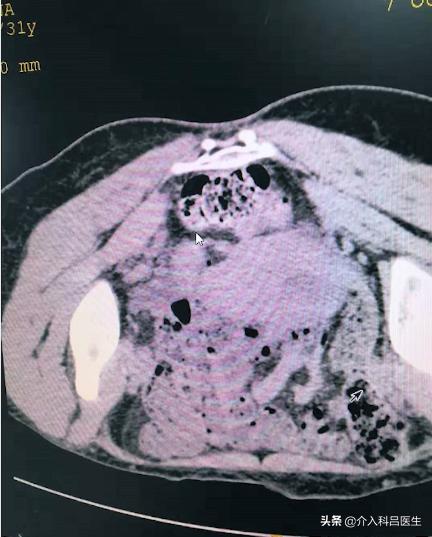

抽出囊液后,我们打酒精硬化。图可以看到巧克力囊肿没了,就剩这么一点了,这是超级微创的一个治疗方法。